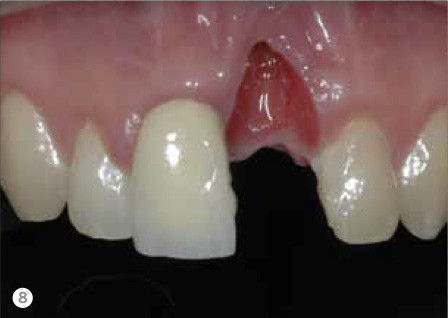

Risk is the potential that a chosen action or activity, including the choice of inaction, will lead to a loss or undesirable outcome. It includes any threat that the patient or clinician could potentially encounter. In dentistry, it takes seconds to destroy and years to reconstruct (Figure 8 and Figure 9), and this reality can be the greatest threat to reconstruction and implant-supported prostheses. When assessing risks, examining the patient through several different risk filters provides a holistic view of the patient’s condition. A patient’s risk may be present in one or many of these filters.

Fig 8 It takes seconds to destroy and sometimes years to reconstruct. This patient had an incorrectly placed implant that created a tremendous defect. Years of surgery and orthodontics were necessary to correct the discrepancy.

Figure 8

Fig 9. It takes seconds to destroy and sometimes years to reconstruct. This patient had an incorrectly placed implant that created a tremendous defect. Years of surgery and orthodontics were necessary to correct the discrepancy.

Figure 9